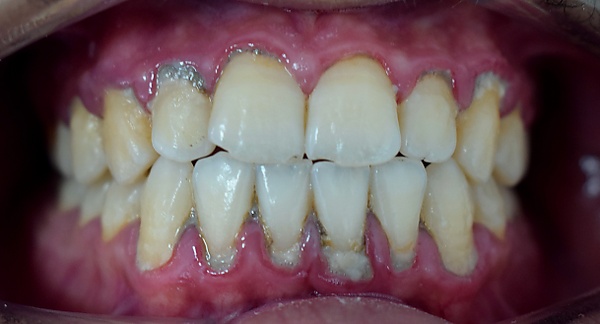

Заболева́ния пародо́нта (заболева́ния периодо́нта)[1][2]  — группа болезней, поражающих пародонт (периодонт)десну, альвеолярный отросток, цемент и периодонтальную связку. В мире распространённость заболеваний пародонта среди людей в возрасте группе 20—44 года составляет 65—95 %, в возрасте 15—19 лет — 55—89 %. В России распространённость среди детей в возрасте 12 лет — 48,2 %, среди взрослых в возрасте 44 лет — 86,2 %, в возрасте 60—65 — до 100 %[3]. Заболевания проявляются зубной болью, чувством выросшего зуба, отёками дёсен и лица; в тяжёлых случаях — недомоганием и лихорадкой[3][4]. Частые осложнения: потеря зубов, некроз челюсти и мягких тканей лица[5].

Пациенты с болезнями пародонта жалуются на зубную боль, отёк десны, чувство выросшего зуба, отёк лица; в тяжёлых случаях — на повышенную температуру тела, недомогание. Общие клинические признаки заболеваний пародонта — потеря эпителиального прикрепления зуба, подвижность зуба, большая глубина десневого кармана, гингивит, кровоточивость при зондировании, неприятный запах изо рта; при некротических заболеваниях — некроз дёсен, изъязвление межзубных промежутков, остеонекроз, регионарная лимфаденопатия[3][4][15].